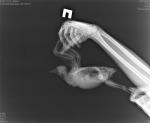

Мирабель Опубликовано 14 марта, 2017 Автор #56 Опубликовано 14 марта, 2017 Я вчера отвезла ее в ветклинику, сделали рентген, врач сказал что у нее затемнение в воздухоносных мешках, кишечник тоже не очень и зоб растянут сказала. В трахее все чисто. Короче назначила лечение, анализы будем 15 числа сдавать.Сегодня состояние нормальное вполне, бегает по кухне пытается взлететь. Правда голову сильно закидывает назад, по Ньюкасла у нас улучшений нет, а мне кажется даже немного ухудшения, наверно потому что он попал ко мне в самом начале болезни самом. Когда нервничает сильно голову закидывает назад и пятиться задом(( вот на фото наша любимая поза(( Врач тоже про доксициклин говорила, но сказала что его как бы с острожностью, но если надо будет то будем применять, пока сказала стандартную противобактериальную терапию попробуем на байтриле. Нистатин оставила, и пару дней фуросемид потому что сказала тяжело дышать ей. Сказала что при таком состоянии может быть что угодно из инфекций вплоть до туберкулеза.

маленький принц Опубликовано 15 марта, 2017 #60 Опубликовано 15 марта, 2017 снимок рентгена крупно выложите

Мирабель Опубликовано 16 марта, 2017 Автор #61 Опубликовано 16 марта, 2017 Маленький принц, мы завтра поедем на прием и я попрошу скинуть на флешку рентген, т. к. на руки его не дали. Я еще хотела спросить у Вас про семечки в виде лакомства их в кожуре насыпать или очищенные?А вообще я ставила тарелки с зерном и воду она когда бегает, такое чувство что под ноги не смотрит бегает по всему подряд и по зернам и по воде..поэтому я все убрала пока, но хочу попробовать все же приучать ее клевать что-то. На днях я ее кормила и она схватила клювом пучок ниток торчащих с майки возле ее клюва))это было неожиданно)))

Мирабель Опубликовано 18 марта, 2017 Автор #77 Опубликовано 18 марта, 2017 Даша, спасибо большое за такой подробный ответ. Особенно за 2 зернышка перловки 25 раз хоть сравню порции какие я ей даю, а то эти ложки столовые меня с ума сводят, столовая ложка с горки и без горки это достаточно разное кол-во зерна по объему. По поводу семечек - это так от нечего делать обсуждали, хотела просто попробовать дать будет она интерес проявлять или нет. я кормлю ее в основном пшеницей и перловкой+ добавляла корм для попугаев небольшую часть и гречки. По поводу кормления я пыталась и в баночку и рюмочку,и тарелку глубокую ставила, подносила еду под самый клюв - 0 реакции не пробует даже клевать, поэтому я пока не ставлю корм и кормлю вручную, тем более по коробке она все время бегает по периметру час и больше иногда. Но ей же надо двигаться, я думаю это нормально. По комбилипену ситуация такая, я его купила но не давала, потому что я сравнила состав комбилипена и гамавита, и в гамавите содержатся все те же вит группы В что и в комбилипене, поэтому я давала гамавит. Сейчас перейду на комбилипен, т к купила второй флакон гамавита, а он чет испортился, стал бледным выкинула. По поводу хрипов их слышно и так, и как раз первый хрип был после того как я выпустила очередной раз погулять и она замахала крыльями и тут же захрипела закашляла, и с этого началось, часто когда подхожу к ней она "хрюкает" может дышать начинает сильнее, бывает при надавливании на спину этот звук. Такое ощущение что у нее слизь на пути у воздуха что ли.. Врач вчера смотрела ей глотку специальным прибором который увеличивает и освещает одновременно, сказала что есть немного слизь прозрачная и небольшой участок как бы воспаление но маленький, а в основном нормальная розовая слизистая. Лекарства следующие:1. Байтрил 2,5% по 0,06 1 раз в день 15 дней всего2. Добавила преднизолон т к улучшений не было на байтриле 0,1 развести до 1 мг и давать по 0,1 мг 2 раза 2 -3 дня не больше3. Нистатин еще 4 дня (но я боюсь его бросать, буду до конца антибиотиков давать)4. Ветом на кончике ножа Байтрил с 13.03 5 дней получается, сегодня 6 день еще не давала ей.Что скажите по дозировке байтрила?? Птица сегодня хрипит больше чем вчера и позавчера. Выкладываю рентген кому интересно. P.S. Пожалуйста, скажите как сделать небольшую цитату из текста? я на форумах не сижу, не могу понять как это сделать у меня на кнопке цитата цитируется весь предыдущий ответ.